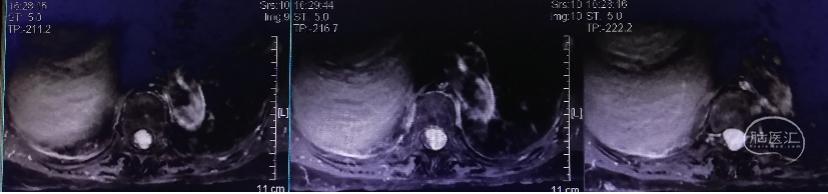

图1.X光定位病变节段

图1.X光定位病变节段 图2.胸椎内固定